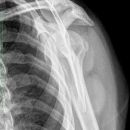

Dislozierte subcapitale Fraktur mit Tbc majus